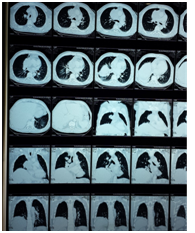

Male 55 years of age, genetic burden to you, dm, heart disease. Tab up to 6 months 5 cigarettes a day for 15 años. PA Starts 4 months myalgia and arthralgia, headache with decubitus, dizziness, dry cough without predominance of time, wheezy, hyperoxia, tired, exhausted, insomnia, lateropulsion, dorsalgia .disfonía ago , dyspnea small efforts, night sweats, back pain, facial edema, lower limb, abominal, upper limb and neck EFTA 90/60, FC 120X MIN, facial edema and neck, even sitting jugular plethora, thoracic venous network, adenomegalia bilateral neck and underarm, edema and abdominal wall members inferiores (Figure 1). He underwent chest CT lung tumor reporting based region right evil-looking, mediastinal tumor with calcifications and data invasion of pericardium and conditioning svcs superior vena cava, mediastinal lymphadenopathy of bilateral hilar groups prevascular (Figure 2) (Figure 3).

Figure 2 Report of CT lung tumor.

Figure 3 Report of CT lung tumor.